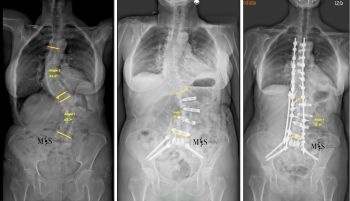

El equipo quirúrgico del Centro Médico Teknon, liderado por el Dr. Christian Morgenstern, director del Morgenstern Institute of Spine en Centro Médico Teknon, ha intervenido con éxito a una paciente de 80 años afectada por una escoliosis degenerativa dorsolumbar severa. El caso, que presentaba una curvatura de 57º en la zona lumbar y 42º en la dorsal, ha sido resuelto mediante la técnica ACR (corrección de columna anterior) en dos tiempos.

La intervención se dividió en dos tiempos quirúrgicos para maximizar la seguridad. En una primera fase, se realizaron abordajes mínimamente invasivos por vía anterior y lateral para rectificar parcialmente la columna, por lo que se logró reducir la curva lumbar de 56º a 39º de forma inmediata. Esta corrección previa permitió que la segunda fase, realizada por vía posterior, fuera mucho menos agresiva y pudiera ejecutarse de forma percutánea.